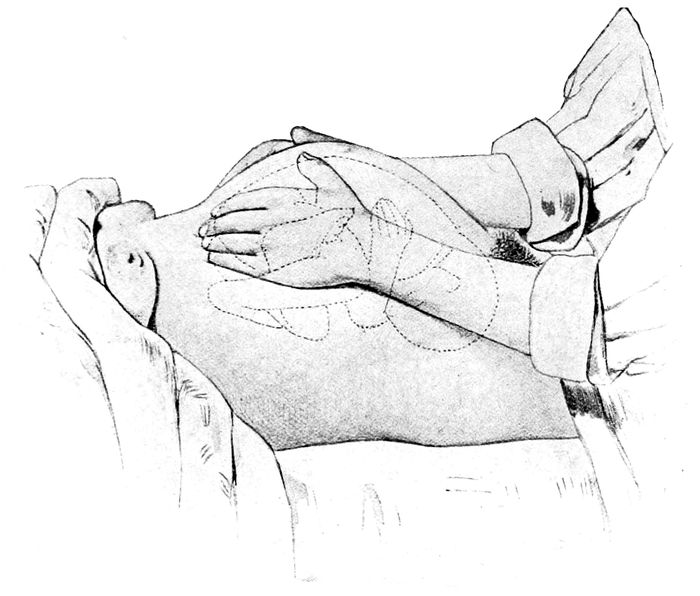

Palpation. What is in the pelvis? |

134 |

| |